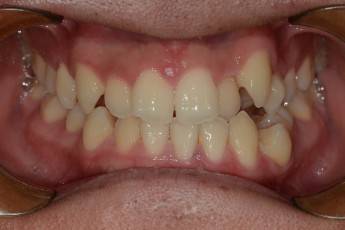

Before

After